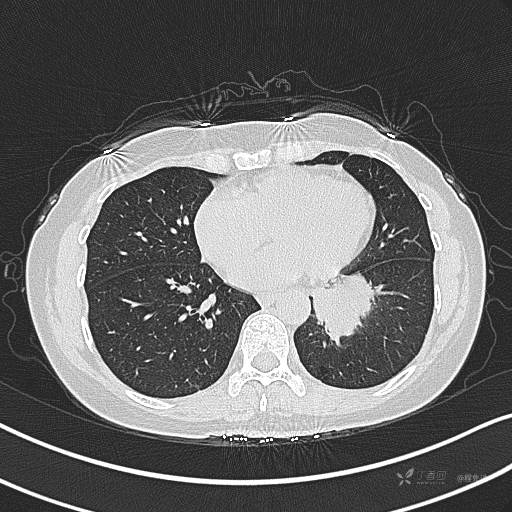

CT平扫

肺窗